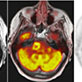

PET / MRI Scan

UCSF’s PET/MRI brings cutting-edge technology to the clinic. This new technology combines time-of-flight PET with 3-Tesla MRI for exceptional image quality, more conclusive diagnosis, and lower radiation in a single exam. The powerful combination of molecular, functional and anatomic information provides essential data for critical treatment decisions.